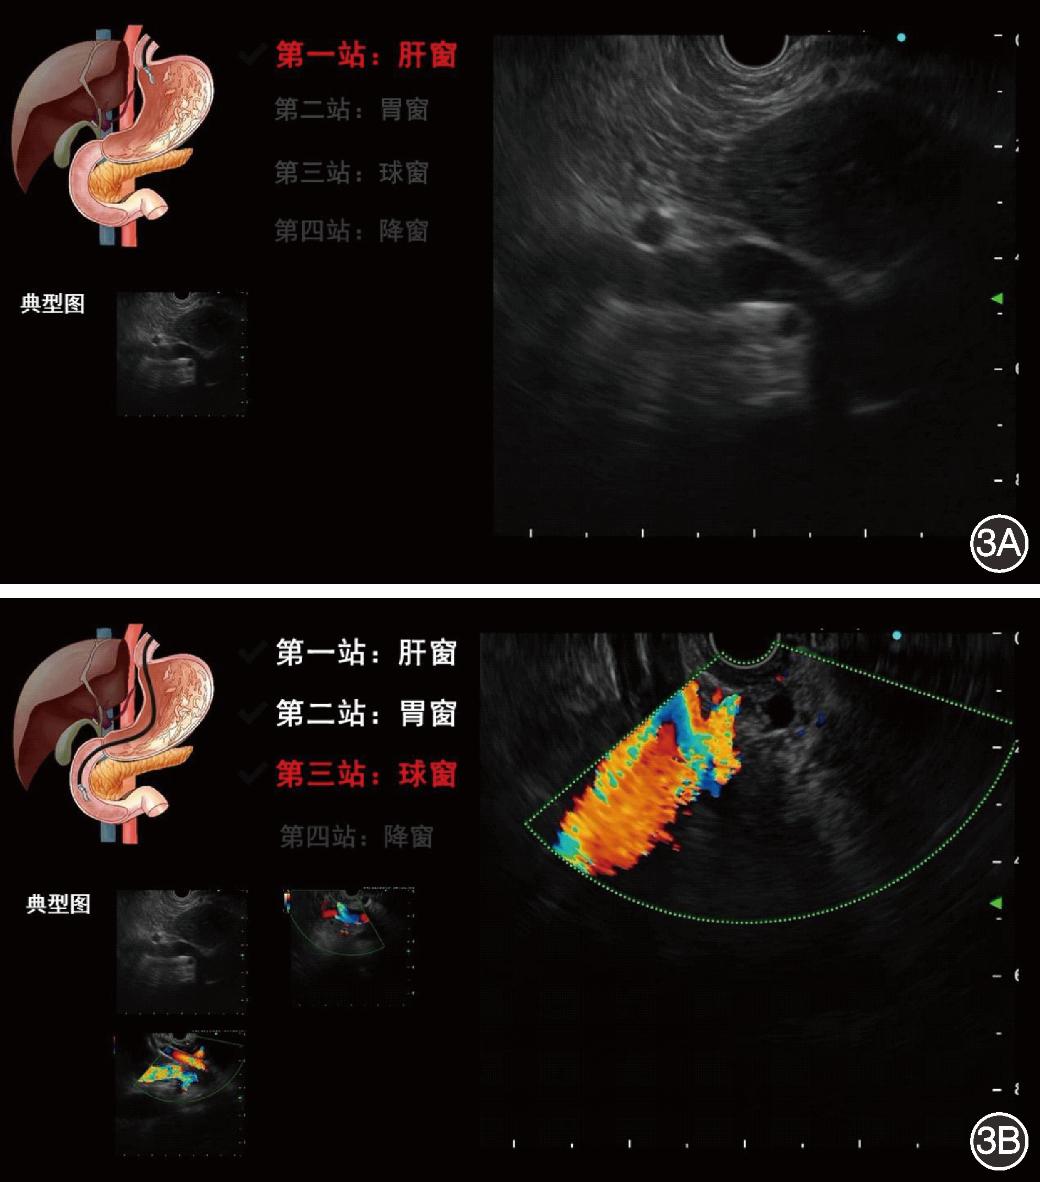

5.模型整合为系统:将模型进行封装整合,构建成为人工智能胆管扫查辅助分站系统,在进行EUS时,自动导入检查视频,可以实时提醒医师扫查站点覆盖情况(图3)。

图3 内镜超声胆管扫查辅助分站系统自动分站界面展示 3A:当扫查到肝窗时,肝窗被点亮,左下角保留了1张肝窗典型图;3B:已完成肝窗、胃窗的扫查,正在扫查并点亮球窗,左下角分别保留了肝窗、胃窗和球窗的1张典型图片